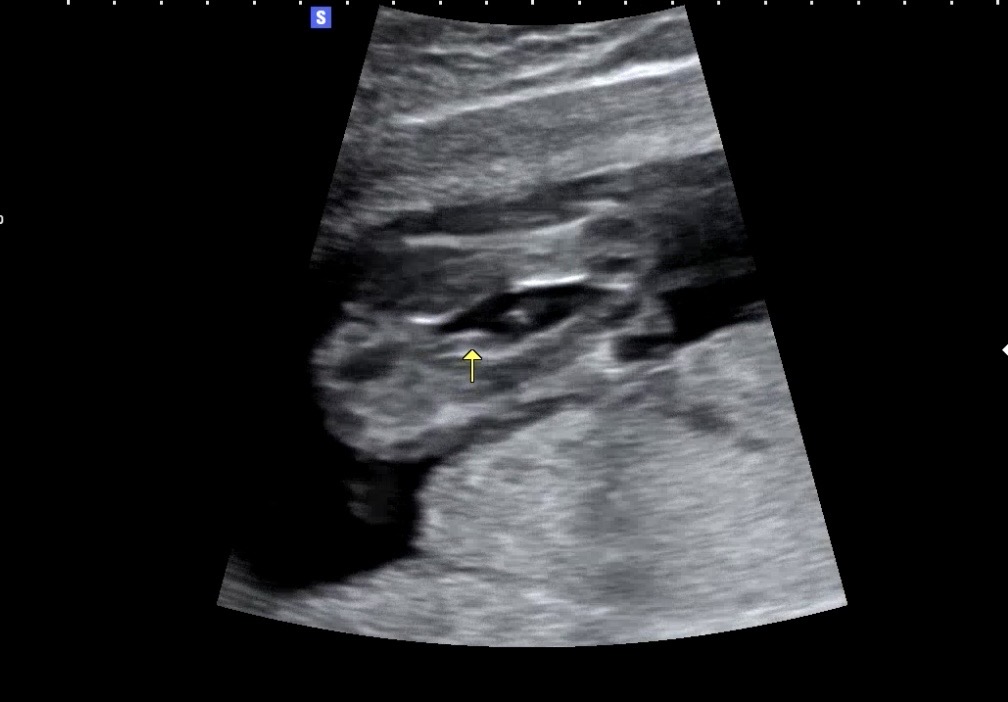

16주 다리사이 추측도와주세요ㅠㅠ

아기가 다리를 모으고있어서 잘 안보이는데 딸일까요 아들일까요?